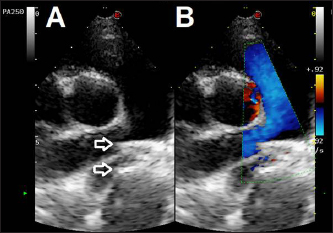

Thoracic radiographs showed left-sided cardiomegaly and pulmonary over circulation (Fig. 1). A transthoracic echocardiogram revealed severe left atrial and left ventricular dilation: left atrium/aorta (LA:Ao): 2.04, reference value: <1.6, normalized left ventricular internal diastolic diameter (LVIDDN): 3.02, reference value: ≤1.7) and large PDA, with an approximate minimal ostium and ampulla diameters of 5.2 and 10.3 mm (Fig. 2). Doppler echocardiography confirmed left-to-right flow across the PDA with a pressure gradient of 102 mmHg in systole and 41 mmHg in diastole. Mild mitral regurgitation was also noted.

Fig. 1. Thoracic radiographs, right lateral and dorso-ventral views, (A and B) before the surgery and (C and D) 24 hours later. Post-operative films show a reduction of the cardiac silhouette and of the pulmonary over-circulation, and correct device position.